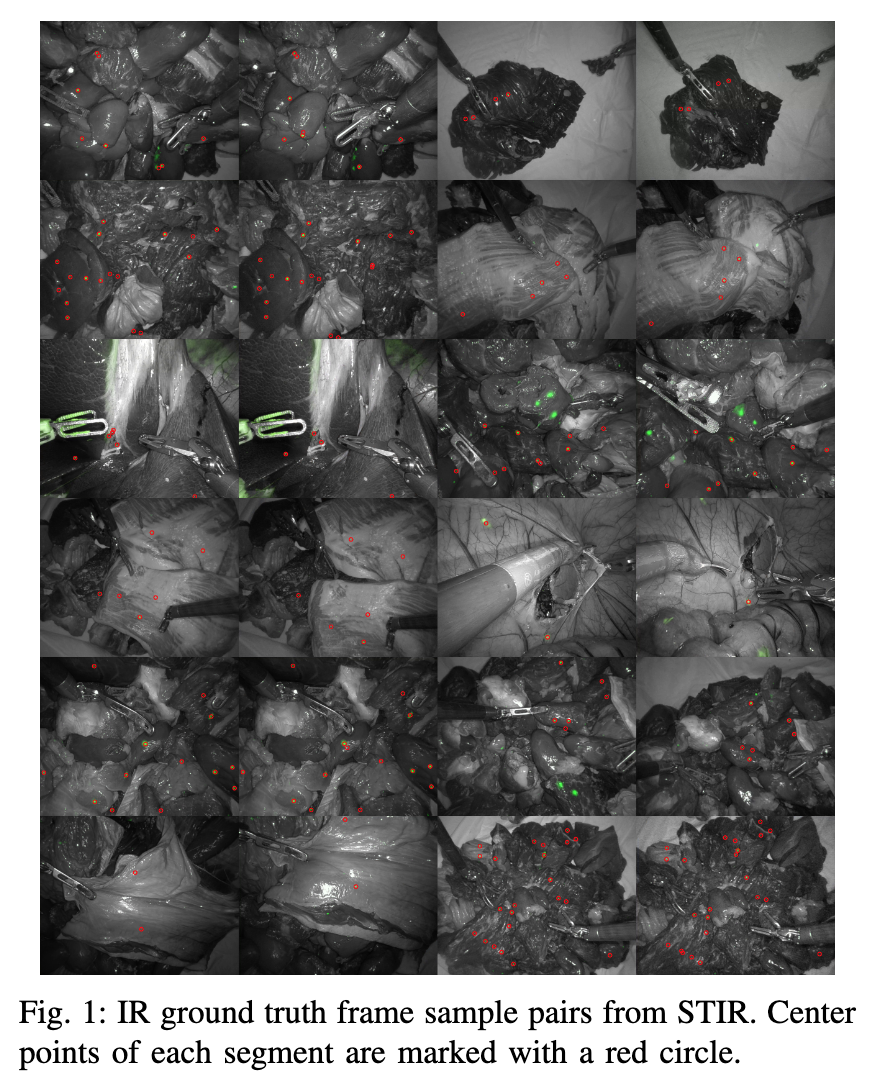

| STIR: Surgical Tattoos in Infrared Authors Adam Schmidt, Omid Mohareri, Simon DiMaio, Septimiu E. Salcudean 量化内窥镜环境中跟踪和绘制组织的方法的性能对于实现医疗干预和手术的图像引导和自动化至关重要。迄今为止开发的数据集要么使用严格的环境、可见的标记,要么要求注释者在收集后标记视频中的显着点。这些分别是不通用的、对算法可见的、或者成本高昂且容易出错的。我们引入了一种新颖的标记方法以及使用该方法的数据集,即红外 STIR 中的外科纹身。 STIR 具有持久性但对可见光谱算法不可见的标签。这是通过用红外荧光染料、吲哚菁绿 ICG 标记组织点,然后收集可见光视频剪辑来完成的。 STIR 包含数百个体内和离体场景的立体视频剪辑,并在红外光谱中标记了起点和终点。 STIR 拥有 3,000 多个标记点,将有助于量化并更好地分析跟踪和绘图方法。介绍 STIR 后,我们使用 3D 和 2D 端点误差和准确性指标来分析 STIR 上多种不同的基于帧的跟踪方法。 |